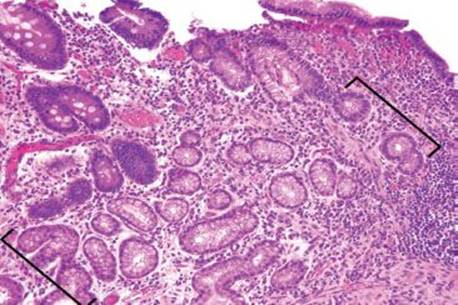

Figure 3.64 Acute ileitis pattern, active chronic granulomatous ileitis, Crohn disease. At low power, crypt shortfall with basal lymphoplasmacytosis is seen: note that the crypts fall short of the muscularis mucosae (arrowheads) because of a basal layer of lymphoplasmacytic inflammation (bracket). Granulomata in Crohn disease (asterisk) can be notoriously difficult to appreciate in intensely inflamed specimens, as in this case. In contrast to normal terminal ileum architecture, note that it would be impossible to strip off the overlying epithelium in this case since the epithelium is inseparably melded to the associated active chronic inflammatory injury. Contrast this image with normal architecture (Figs. 3.20–3.25).

Figure 3.65 Acute ileitis pattern, active chronic granulomatous ileitis, Crohn disease. On higher power a granuloma with foreign body giant cells is more easily appreciated (bracket). AFB and GMS special stains were negative.